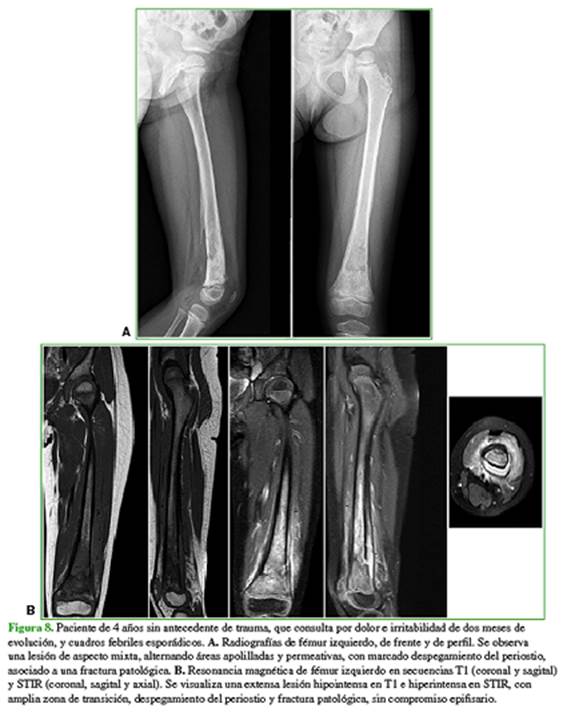

Los diagnósticos diferenciales más frecuentes son otros sarcomas, como el de Ewing, o un proceso infeccioso (osteomielitis) (Figura 8).